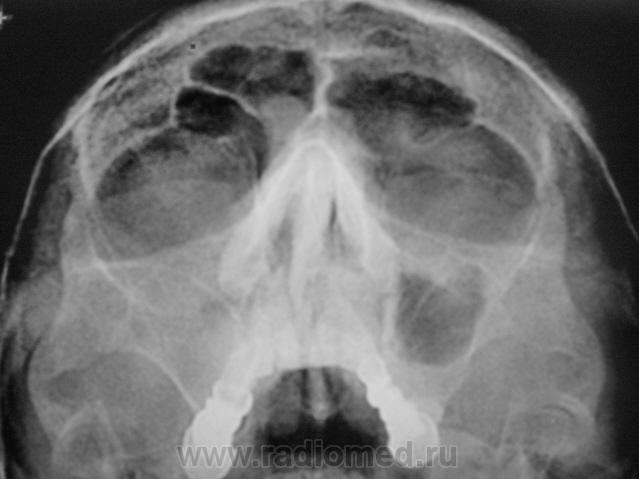

Пациент второй.

Второй случай. уровень слева,субтотальное затенение справа.киста правой половины лобной.....